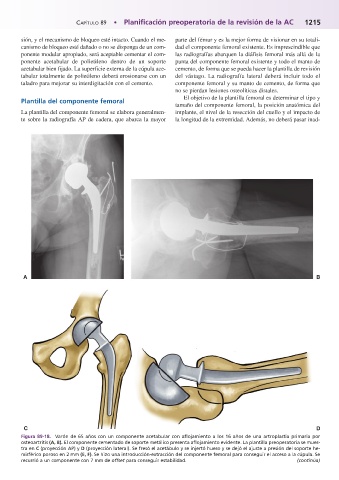

Figura 89-18.mVarón de 65 años con un componente acetabular con aflojamiento a los 16 años de una artroplastia primaria por

osteoartritis (A, B). El componente cementado de soporte metálico presenta aflojamiento evidente. La plantilla preoperatoria se mues-

tra en C (proyección AP) y D (proyección lateral). Se fresó el acetábulo y se injertó hueso y se dejó el ajuste a presión del soporte he-

misférico poroso en 2 mm (E, F). Se hizo una introducción-extracción del componente femoral para conseguir el acceso a la cúpula. Se

recurrió a un componente con 7 mm de offset para conseguir estabilidad. (continúa)